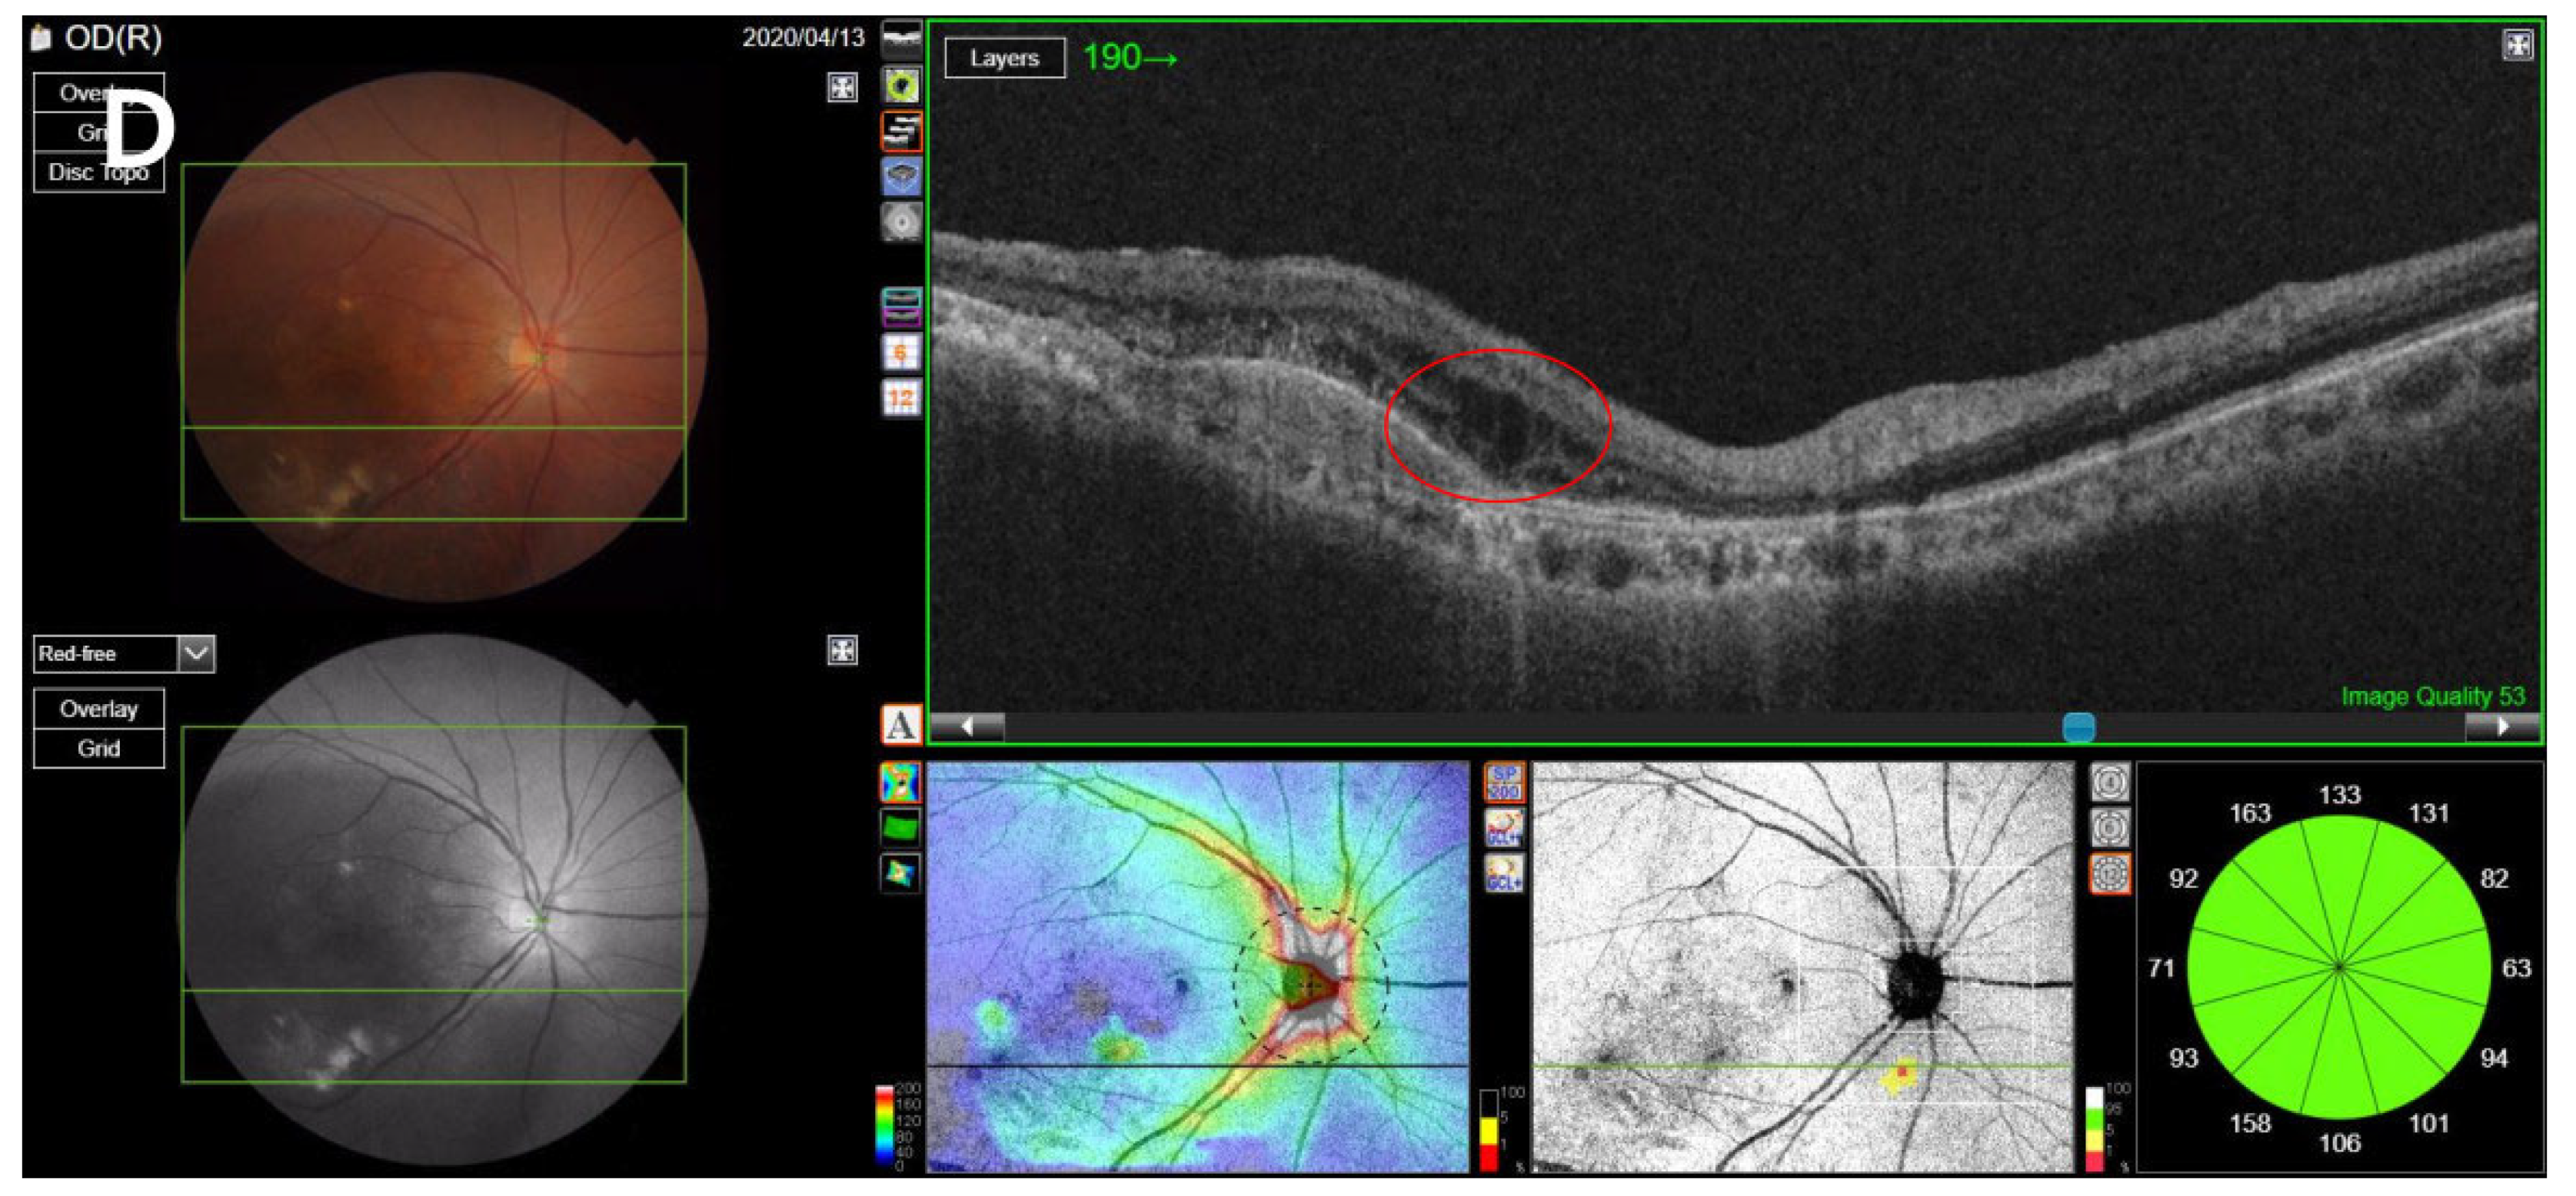

SS-OCT was performed on the enrolled eyes of all included patients using a swept-source DRI OCT Triton Plus (Topcon Co., Tokyo, Japan) at each follow-up point. Using the OCT scans, we recorded the central subfield thickness (CST) and any anatomical abnormalities including accumulated levels of subretinal fluid (SRF), intraretinal fluid (IRF), and subretinal hyperreflective material (SHRM) and presence of pigment epithelial detachment (PED), and measured the maximum height of the SRF and PED. CST, which refers to the average retinal thickness within a 1-mm-diameter ring based on the macula [19], was measured using built-in optical software (IMAGEnet 6 version 1.25.16650; Topcon Co., Tokyo, Japan). Anatomical abnormalities in OCT images, such as the levels of SHRM, SRF, PED, and IRF, were found to indicate exudative disease activity [20,21,22]. For patients with confirmed SRF accumulation or PED, the maximum SRF height (distance between the outer retina and the hyperreflective line of the RPE) was manually measured using the caliper tool in IMAGEnet software; a similar process was repeated to measure the maximum PED height (distance between the inner surface of the Bruch membrane and the outer surface of the RPE) by reviewing the OCT image [23,24] (Figure 1).

Figure 1.

Measurement of SRF, PED, SHRM, and IRF. (A) The maximum SRF height was measured as the maximum distance between the outer retina and the hyperreflective line of the retinal pigment epithelium on the OCT image, using the caliper tool using IMAGEnet software. (B) The maximum PED height was measured as the maximum distance between the inner surface of the Bruch membrane and the outer surface of the retinal pigment epithelium. (C) Presence of SHRM, which is a morphological feature seen on OCT as hyperreflective material located external to the retina and internal to the retinal pigment epithelium. (D) Presence of IRF, which appears as dark cystic accumulations of fluid above the outer plexiform layer. SRF, subretinal fluid; PED, pigment epithelial detachment; SHRM, subretinal hyperreflective material; IRF, intraretinal fluid; OCT, optical coherence tomography.

In anti-VEGF therapy, it is imperative to maintain an adequate injection interval to control disease activity [28,29]. Some studies evaluating the changes in intravitreal injection therapy during the COVID-19 pandemic have consistently shown that intravitreal injection was not administered on time during this period [12,13,14]. Yang et al. [14] reported that the BCVA of patients was worse during the pandemic period than before, and Sevik et al. [12] found that BCVA and OCT disease activity worsened in patients with a delayed injection after the end of the COVID-19 lockdown period. Although some studies have investigated nAMD patients with delayed treatment due to COVID-19, to our knowledge, this is the first study to evaluate the clinical prognosis, including the quantitative analysis of anatomical abnormalities, by tracking nAMD patients with delayed intravitreal anti-VEGF injections due to COVID-19 for up to 6 months after the delayed injection date. Borrelli et al. [30] tracked nAMD patients up to two consecutive follow-ups after the COVID-19 pandemic to evaluate the short-term changes in the clinical course of nAMD patients due to the spread of COVID-19. They found that the follow-up interval increased due to COVID-19, the BCVA worsened, and the longer the visit time was delayed, the worse the BCVA. Similarly, in this study, BCVA significantly worsened after the COVID-19 outbreak compared to before the outbreak, but no association was observed between the injection delay time and the degree of BCVA deterioration. Elfalah et al. and Naravane et al. [15,16] compared the BCVA and CST before and after treatment delay in patients of various disease groups whose intravitreal injection was delayed due to COVID-19. In the case of nAMD patients, the BCVA worsened after a treatment delay in both studies, but CST decreased in one of the studies [15] and increased in the other study [16]. This difference between the two studies and the current study can be attributed to the fact that the two studies only analyzed a single time after the treatment delay. In the study by Yeter et al. [8], which is most similar to our study, the authors analyzed the changes in BCVA, CST, and OCT findings by following, up to an average of 3.5 months, nAMD patients with delayed intravitreal anti-VEGF injection. The authors reported that the injection interval shortened after the delay, and the CST and SRF, IRF, and SHRM levels increased initially, but decreased as the treatment started again, but the BCVA did not recover as much as before the treatment delay. Similarly, in our study, the injection interval decreased after the delay in injection, and the OCT findings deteriorated at the time of the injection delay, but improved after treatment resumed. Additionally, at a follow-up of 6 months after the treatment delay, the visual acuity did not recover as much as the baseline. However, in our study, the BCVA and OCT findings temporarily recovered and then worsened again during the 6-month period; particularly, the amount of SRF increased significantly (Figure 4).

Figure 4.

OCT change in a patient with neovascular age-related macular degeneration. (A) Baseline OCT image. (B) OCT image at the time of delayed injection. (C) Two months after the delayed injection. (D) Four months after the delayed injection. (E) Six months after the delayed injection. At the time of delayed injection, the BCVA was worse than the baseline, and the maximum SRF height (green line) was higher. After resumption of treatment, the BCVA and SRF height gradually improved, but eventually did not recover to baseline levels after 6 months after the treatment delay. OCT, optical coherence tomography; BCVA, best-corrected visual acuity; logMAR, logarithm of the minimum angle of resolution; SRF, subretinal fluid.